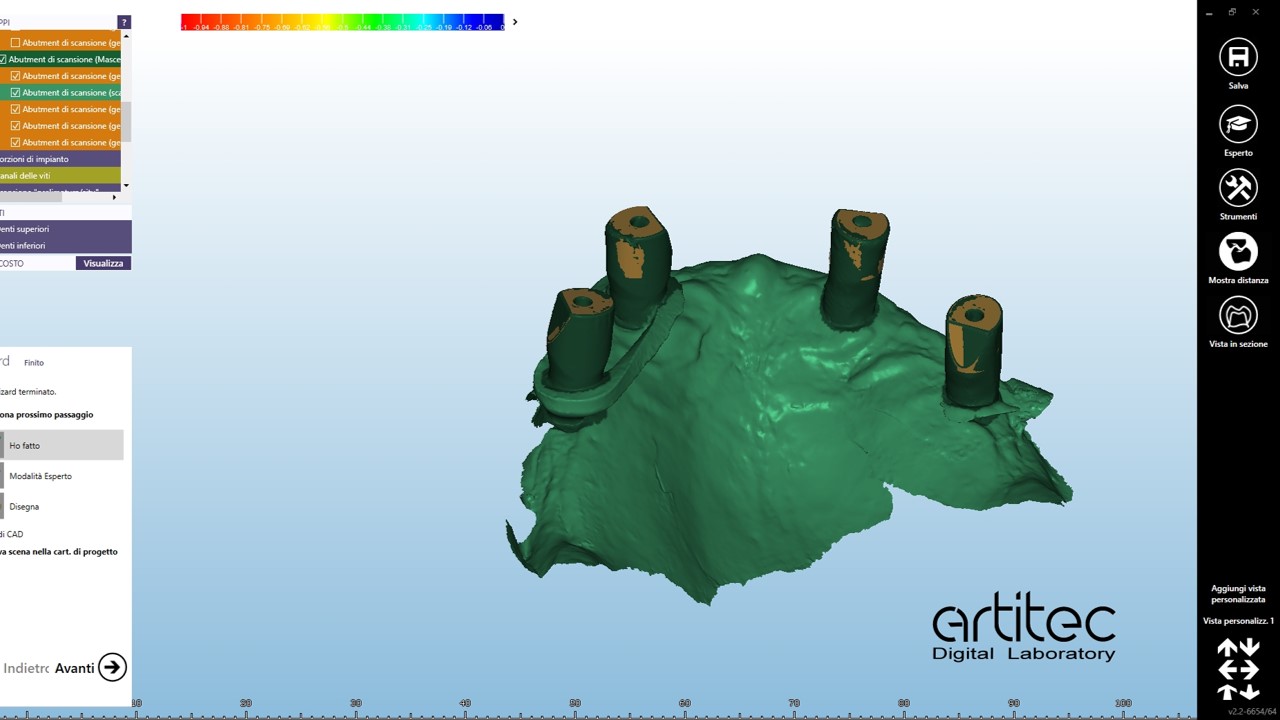

foto 09 scan body superiore

foto 10 scan body superiore allineati- best fit

foto 11 scan body inferiore

foto 12 scan body inferiore allineati

La fase protesica inizia con la ribasatura delle protesi provvisorie per rilevare la corretta anatomia della cresta. Quindi si procede a scansionare con scansione intraorale le impronte ottenute fuori dal cavo orale, poi le protesi provvisorie ribasate ricollocate nel cavo orale e la loro occlusione. Infine, si scansionano le creste edentule dopo aver posizionato gli scan body per tecnica digitale per rilevare la posizione degli impianti. Per la pianificazione sono scattate delle fotografie intraorali ed extraorali per la definizione dei limiti perimetrali del volto al fine di poter eseguire la programmazione del caso tramite il software di previsualizzazione. Le scansioni così ottenute sono poi inviate al laboratorio per la realizzazione di un prototipo delle protesi in prova.

Nell’ultimo incontro prima della finalizzazione delle protesi si verifica la passività ed il corretto accoppiamento protesico di barre in CrCo laser melting sulla base delle quali successivamente sono realizzate le barre in fibra di vetro continuo stampata in 3D. (fig.16-21)